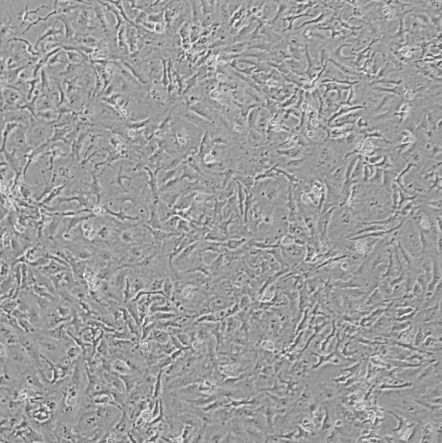

细胞名称:BICR 16_人鳞状细胞癌

细胞形态:上皮样

培养条件:DMEM + 2mM Glutamine + 10% Foetal Bovine Serum (FBS) + 0.4 µg/ml Hydrocortisone

37 ℃, 5% CO2

传代方法:1:2传代,2-3天传1代